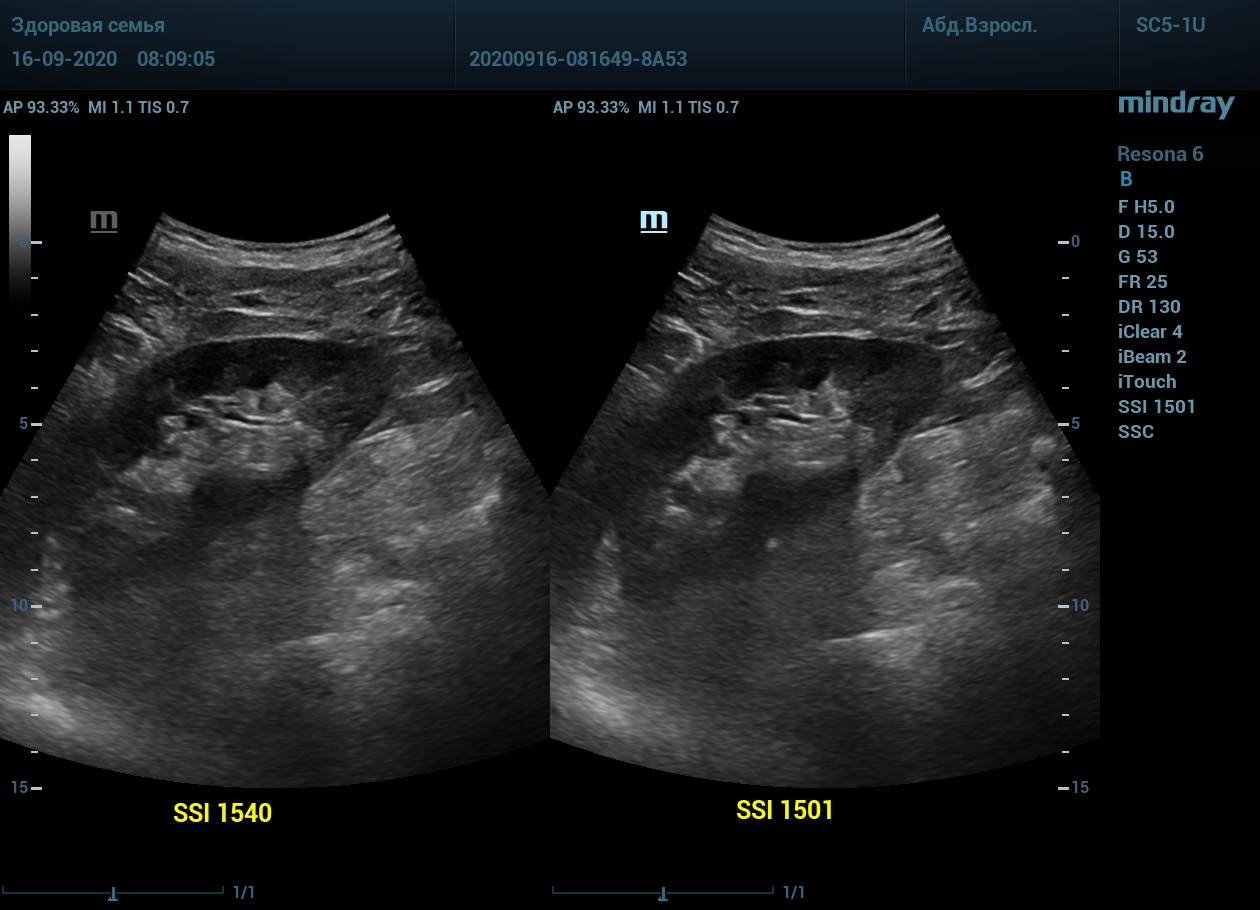

Примеры изображений:

1. Пациент с метеоризмом и большой массой тела. Визуализация поджелудочной железы до и после калибровки скорости ультразвука. Контуры головы и тела железы видны гораздо лучше.